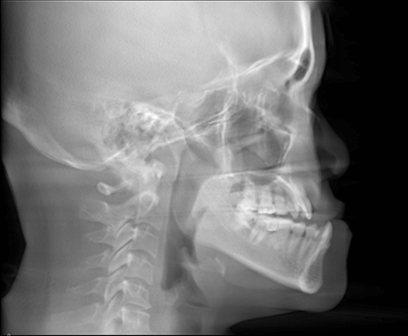

Sleep disordered breathing (SDB) is a term that describes breathing difficulties during sleep.